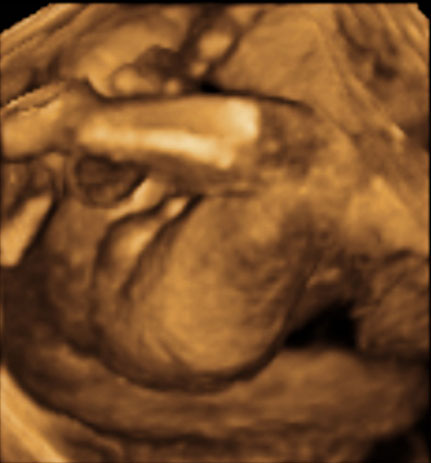

Ecografía 3D de la semana 20: Genitales de un niño

Imagen de genitales masculinos en tres dimensiones en una ecografía en 4D en la 20ª semana de gestación.

Sexo fetal masculino: escroto del bebé